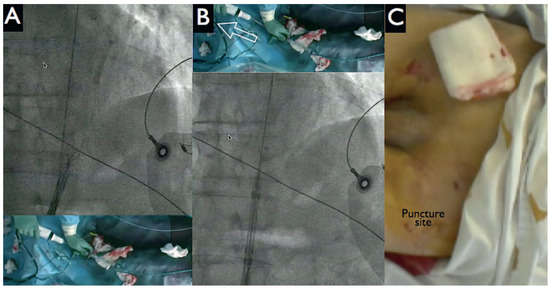

HeartMate PHP Axial Pump for High-Risk PCI

by Diego Arroyo, Serban Puricel, Mario Togni and Stéphane Cook

Cardiovasc. Med. 2016, 19(9), 241; https://doi.org/10.4414/cvm.2016.00430 - 21 Sep 2016

Percutaneous left ventricular assist devices (pVADs) can provide temporary circulatory support during high-risk percutaneous coronary interventions (PCIs). We describe the first case in Switzerland of high-risk PCI with a new pVAD, the HeartMate PHP axial pump (St Jude Medical). Full article